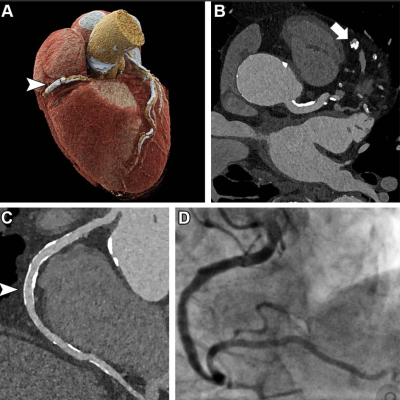

Ultrahigh-resolution (UHR) coronary CT angiography (CCTA) in an 85-year-old man before transcatheter aortic valve replacement. Despite a stent in the right coronary artery and very severe coronary sclerosis with an Agatston score of 4162, diagnostic visualization of the coronary arteries succeeded, and obstructive coronary artery disease was excluded on CT images. (A) Three-dimensional cinematic rendering of the heart. The stent (arrowhead) is visible in the middle segment of the right coronary artery. (B) UHR CCTA with 0.2-mm axial sections. The lumen (arrow) of the severely calcified distal left anterior descending artery can be assessed without artifacts. (C) Curved multiplanar reformations of the right coronary artery with a diagnostic display of the stent lumen (arrowhead). (D) Invasive coronary angiography enables exclusion of in-stent stenosis. Image courtesy of RSNA

Coronary CT angiography (CCTA) is highly effective for ruling out coronary artery disease in patients at low or intermediate risk for the disease. Unfortunately, CCTA in a high-risk population is difficult due to a high prevalence of coronary calcifications and stents.

Coronary calcifications tend to “bloom” on CCTA, making them appear more extensive than they really are. This results in overestimation of blockages and plaque and false-positive results.

Ultra-high-resolution coronary CT angiography (UHR-CCTA) is a promising tool for the noninvasive assessment of patients at high risk for coronary artery disease. Because it uses recently introduced photon-counting CT scanners, it has not been extensively studied.

Dr. Hagar and colleagues compared the diagnostic accuracy of UHR-CCTA with that of the reference standard of invasive coronary angiography (ICA) in 68 patients. The patients had severe aortic valve stenosis.

UHR-CCTA was highly sensitive and specific for coronary artery disease detection. It delivered a median overall image quality score of 1.5 on the 5-point Likert scale. Almost 80% of segments rated as good or excellent.